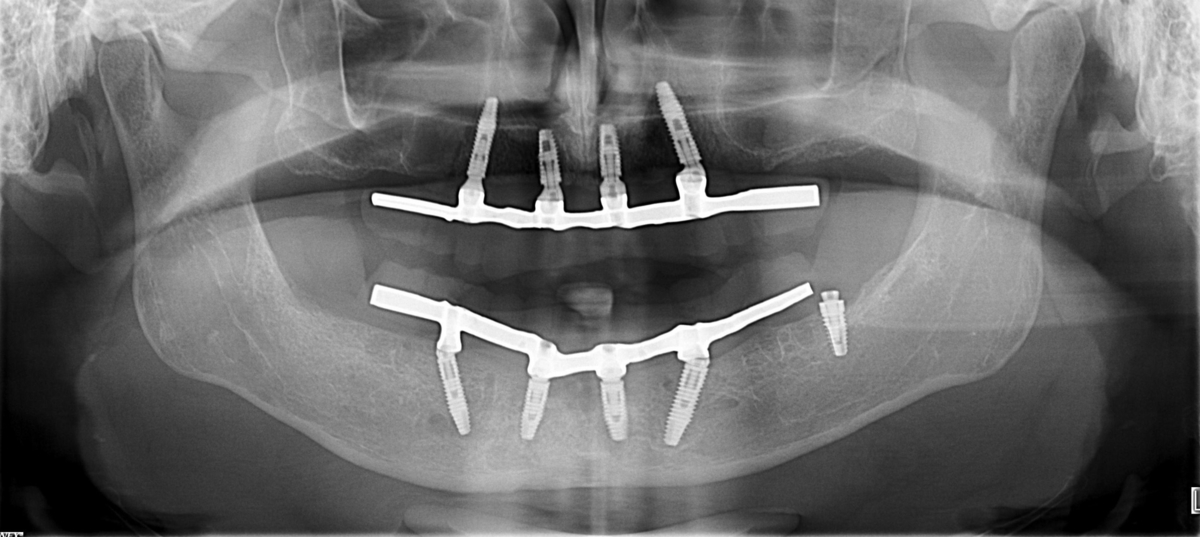

PRÓTESE TOTAL FIXA EM IMPLANTES